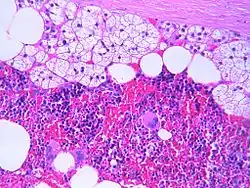

Mikroskopisches Bild eines Myelolipoms mit Nebennierenzellen, Fettzellen und myeloiden Zellen.

Myelolipome sind gelbe bis bräunliche, wenige Millimeter bis 30 cm große, umschriebene, jedoch nicht gekapselte Tumoren. Sie treten üblicherweise solitär und einseitig im Bereich einer Nebenniere auf, werden selten jedoch auch bilateral und/oder außerhalb der Nebenniere (z. B. im Retroperitoneum, Mediastinum, der Leber, in Muskelfaszien) gefunden. Mikroskopisch setzt sich der Tumor aus reifem Fettgewebe und myeloiden Zellen zusammen. Gelegentlich werden Infarktareale, Einblutungen oder knöcherne Metaplasien beobachtet.[1][2]